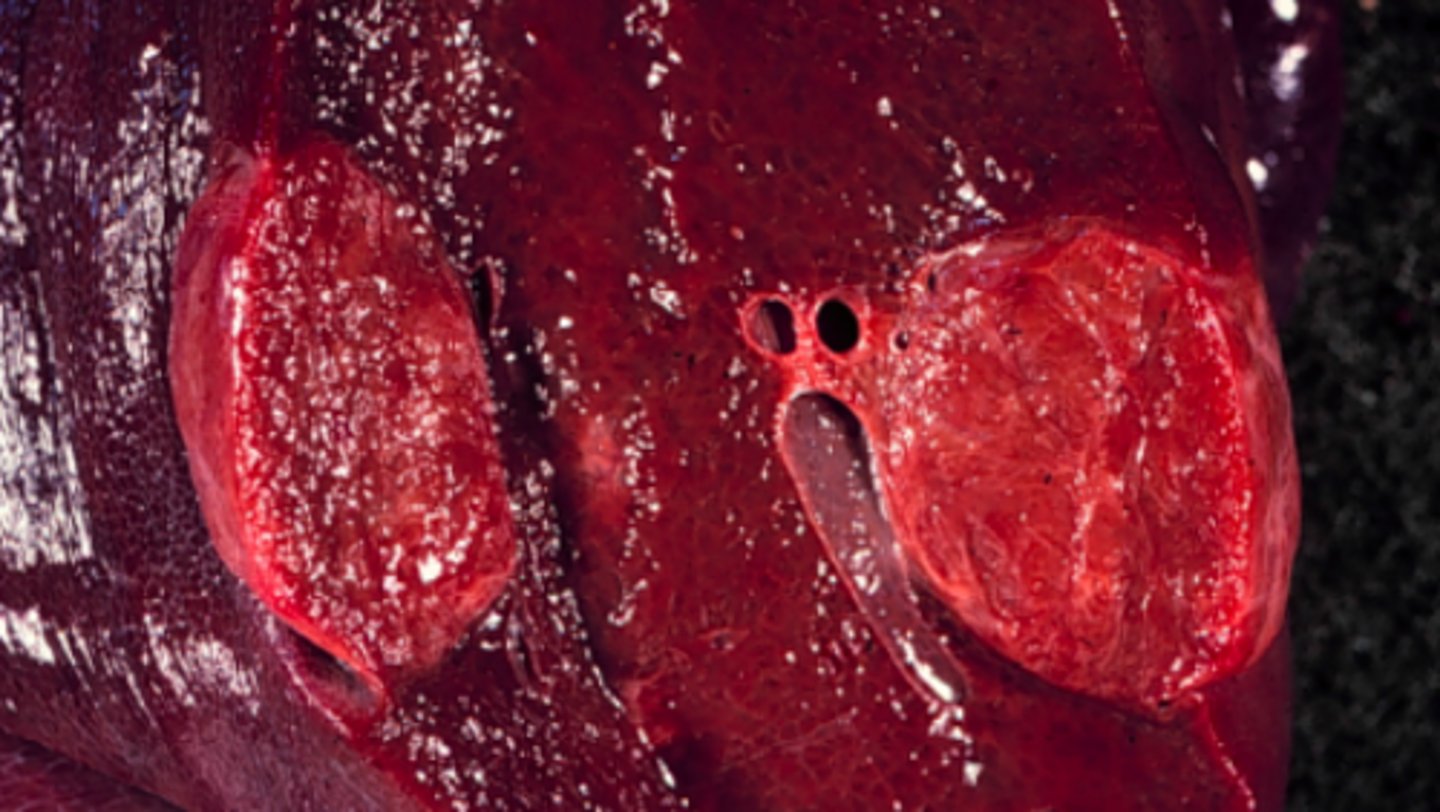

Kortikal adenom, solitært i den ene binyrer. Atrofi af den kontralaterale adrenale cortex

Gennemskåret binyrer fra okse, hvad er den patoanatomiske diagnose?